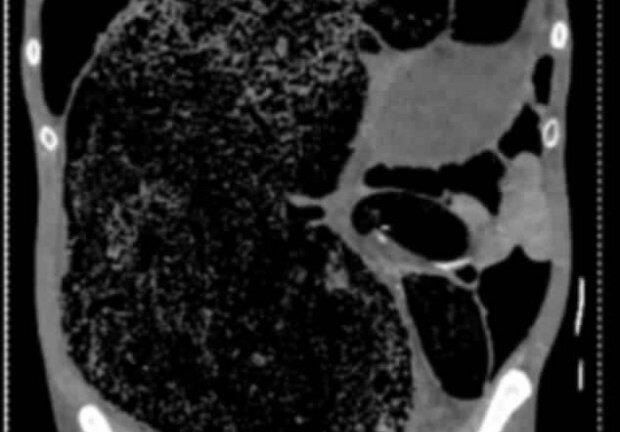

Một bệnh nhân 57 tuổi tại Úc đã thoát chết khi bị 2 lít phân tích tụ trong cơ thể sau 3 ngày táo bón.